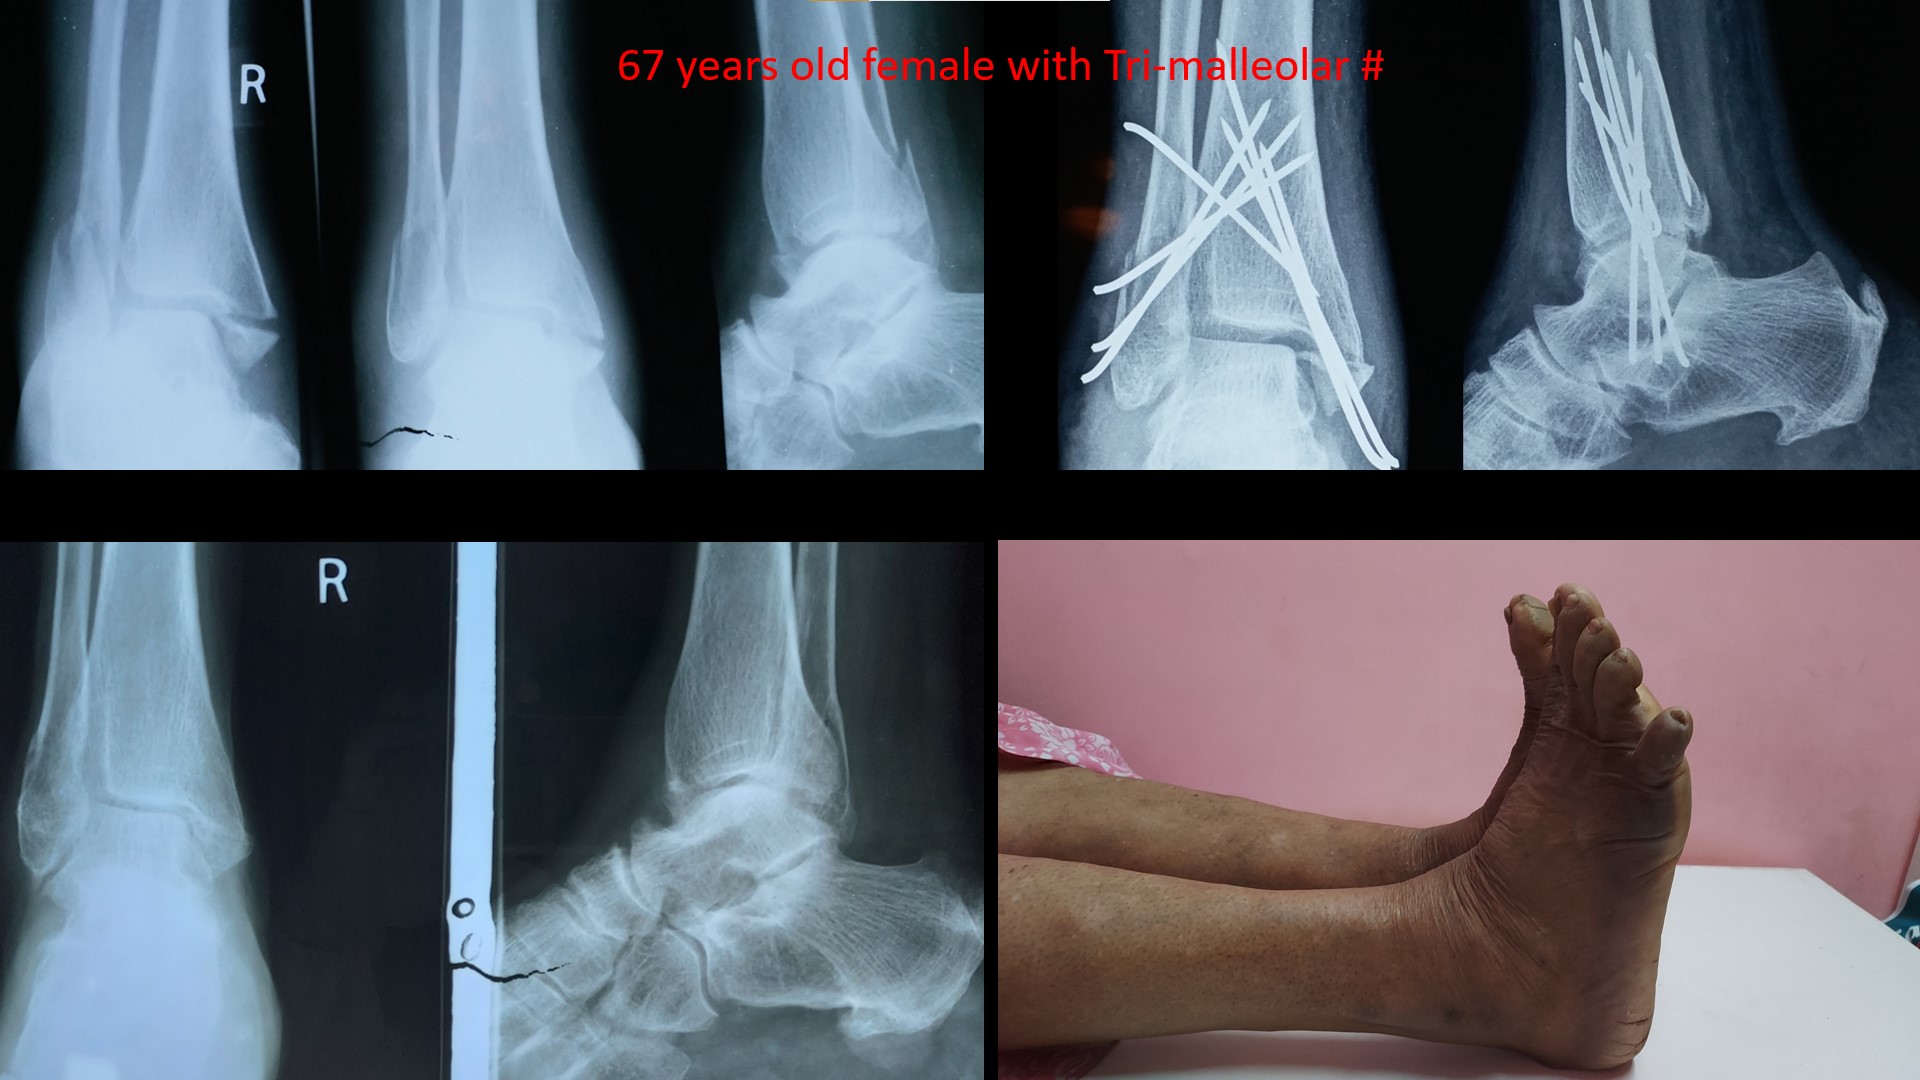

ANKLE